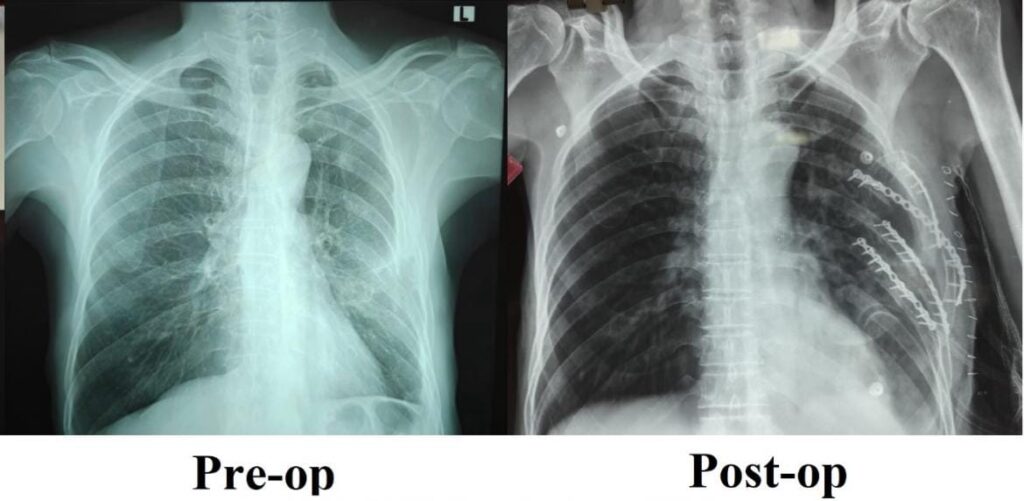

சாலை விபத்து ஒன்றில் சிக்கிய நோயாளி ஒருவருக்கு விலா எலும்புகள் பல இடங்களில் உடைந்திருந்தன. ஒரு மாதத்திற்கும் மேலாக முறையான வலி நிவாரண சிகிச்சைகளும், இயன்முறை சிகிச்சைகளும் அளிக்கப்பட்ட போதிலும், அவர் தொடர்ந்து கடுமையான நெஞ்சு வலியால் அவதிப்பட்டார். எலும்புகள் சரியாக இணையாததாலும், முறிந்த விலா எலும்புகளின் நிலையற்ற தன்மையாலும், ஆழமாக சுவாசிப்பதில் சிரமம், சரியாக தூங்க இயலாமை மற்றும் அன்றாடப் பணிகளைச் செய்ய முடியாத நிலை அவருக்கு நீடித்தது.

நிலைமையின் தீவிரத்தை உணர்ந்த பொது அறுவை சிகிச்சைத் துறையின் இணைப் பேராசிரியர் டாக்டர் விஜயன் P தலைமையிலான குழுவினர், முறிவுகள் ஏற்பட்டிருந்த விலா எலும்புகளை மீண்டும் சீரமைத்து நிலைநிறுத்தும் சிறப்பு அறுவை சிகிச்சையை இவருக்குமேற்கொண்டனர்.

அறுவை சிகிச்சையைத் தொடர்ந்து, இந்நோயாளி வலி குறைந்து, இயல்பாக சுவாசிக்கத் தொடங்கினார். மிக விரைவாகக் குணமடைந்த அவரால் மீண்டும் தன்னம்பிக்கையோடு இயல்பான பணிகளுக்கு இப்போது திரும்புவது சாத்தியமாகியிருக்கிறது.

பொது அறுவை சிகிச்சைத் துறையின் இணைப் பேராசிரியர் டாக்டர் விஜயன் P. இந்த சிகிச்சை செயல்முறை பற்றி பேசுகையில், “விலா எலும்புகள் வலுவின்றி நீண்ட காலம் நிலையற்று இருப்பது, சுவாசத்தையும் மற்றும் உடல் இயக்கத்தையும் ஒட்டுமொத்த நலத்தையும் கடுமையாக பாதிக்கும். விலா எலும்புகளை அறுவை சிகிச்சையின் மூலம் நிலைப்படுத்தியதால், அவருக்கு வலியைக் குறைத்து, நுரையீரலின் செயல்பாட்டை எங்களால் மேம்படுத்த முடிந்தது. பொதுவான சிகிச்சைகள் பலன் தராதபோது, இதுபோன்ற பயனளிக்கும் நவீன அறுவைசிகிச்சைகளின் முக்கியத்துவத்தை இந்த சிகிச்சை முறையின் வெற்றி உணர்த்துகிறது.” என்றார்.